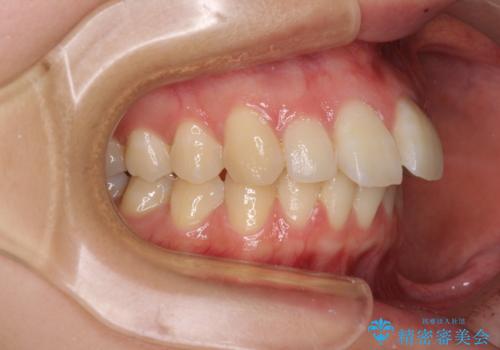

- 前歯の突出感を気にして来院された患者様です。

左右ともに奥歯の咬み合わせが上顎前突となっており、上顎前歯が飛び出している状態でした。

奥歯の咬み合わせ改善が必要であるため、マウスピース矯正より確実に達成のできるワイヤー矯正にて治療を行うこととしました。

奥歯の咬み合わせはしっかりと改善され、前歯の突出感も改善されました。